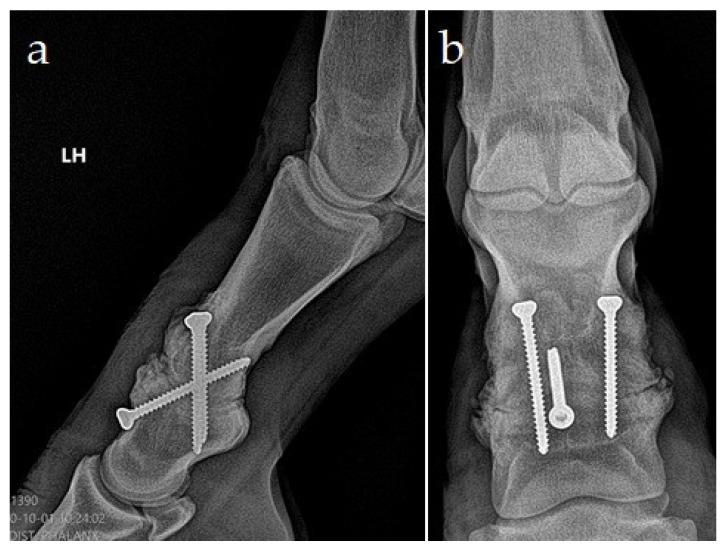

After the medial femoral condyle (MFC), the phalanges are the second most common site for osseous cyst-like lesions (OCLLs). Conservative treatment of phalangeal cysts on the convex surface of proximal phalanx presents a technical problem with access to the stoma of the cyst. Surgical therapy options usually aim to avoid cyst enlargement through drilling or screw placement or to encourage lesion filling with osteoconductive material. This paper describes a case of treatment of the OCLL in a yearling Czech warmblood filly with surgical arthrodesis, together with the packing of the OCLL with calcium phosphate biocement (CPB). The filly showed a chronic, moderate to severe, intermittent left hindlimb lameness. Dynamic examination combined with regional anesthesia and radiography confirmed a clinically significant large OCLL on the distal joint surface of the first phalanx. Treatment of the OCLL was performed by surgical arthrodesis of the proximal interphalangeal joint, using two paraxial and one axial crossed lag screw, after curetting of the cyst and filling with CPB.

除股骨内侧髁外,指骨是骨囊肿样病变(OCLLs)的第二大常见部位。近端指骨凸面指骨囊肿的保守治疗存在囊肿造口难以触及的技术问题。手术治疗方案通常旨在通过钻孔或螺钉置入避免囊肿增大,或促进病灶用骨传导材料填充。本文描述了一匹一岁捷克温血小母马的OCLL采用手术关节固定术治疗的病例,同时用磷酸钙生物骨水泥(CPB)填充OCLL。这匹小母马表现为慢性、中度至重度、间歇性左后肢跛行。动态检查结合区域麻醉和放射摄影证实,第一指骨远端关节面有一个临床上显著的大型OCLL。在刮除囊肿并用CPB填充后,采用两枚近轴和一枚轴向交叉拉力螺钉对近端指间关节进行手术关节固定术,治疗OCLL。